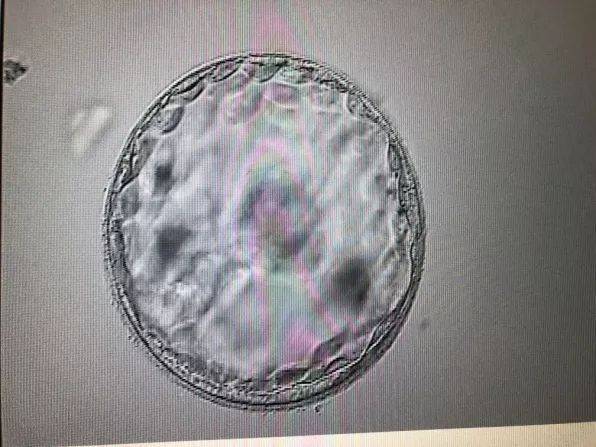

2. 流产风险增加:人流手术可能会增加女性发生自然流产的风险。这是因为人流手术对女性的子宫内膜造成一定的损伤,使得胚胎着床不稳定。